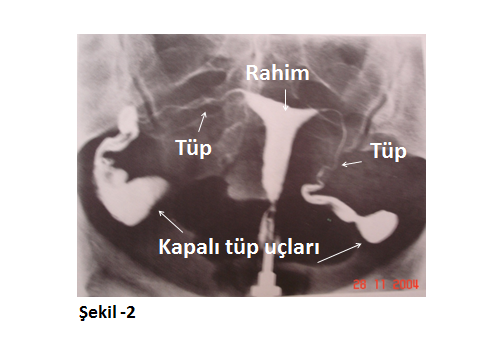

Aşağıda farklı HSG görüntüleri ile konu görsel hale getirilmeye çalışılmıştır.

Şekil-2’deki HSG görüntüsünde ise rahim içi üçgen yapısı ile normal iken; tüp uçları davul tokmağı görünümünde şişlik göstermektedir. Boyalı madde buralarda tutulmuş ve tüplerden geçiş olamamıştır. Bu şiş ve tıkalı tüp uçları tıbbi adı Hidrosalpenks olarak adlandırılır. Bu tablo, genellikle şiddetli karın içi enfeksiyon sekellerinde, bu bölge civarı farklı operasyonlarla bağlantılı nedenlere, vb. oluşabilen bir patolojidir. Hafif tipleri laparoskopik ya da karın açılması yani laparotomik mikrocerrahi ile düzeltilebilir. Ağır tüp hasarlı olgularda ise etkilenmiş tüpler çıkartıldıktan sonra yapılacak Tüp Bebek (IVF) uygulamalarından başarılı sonuçlar alınabilir.